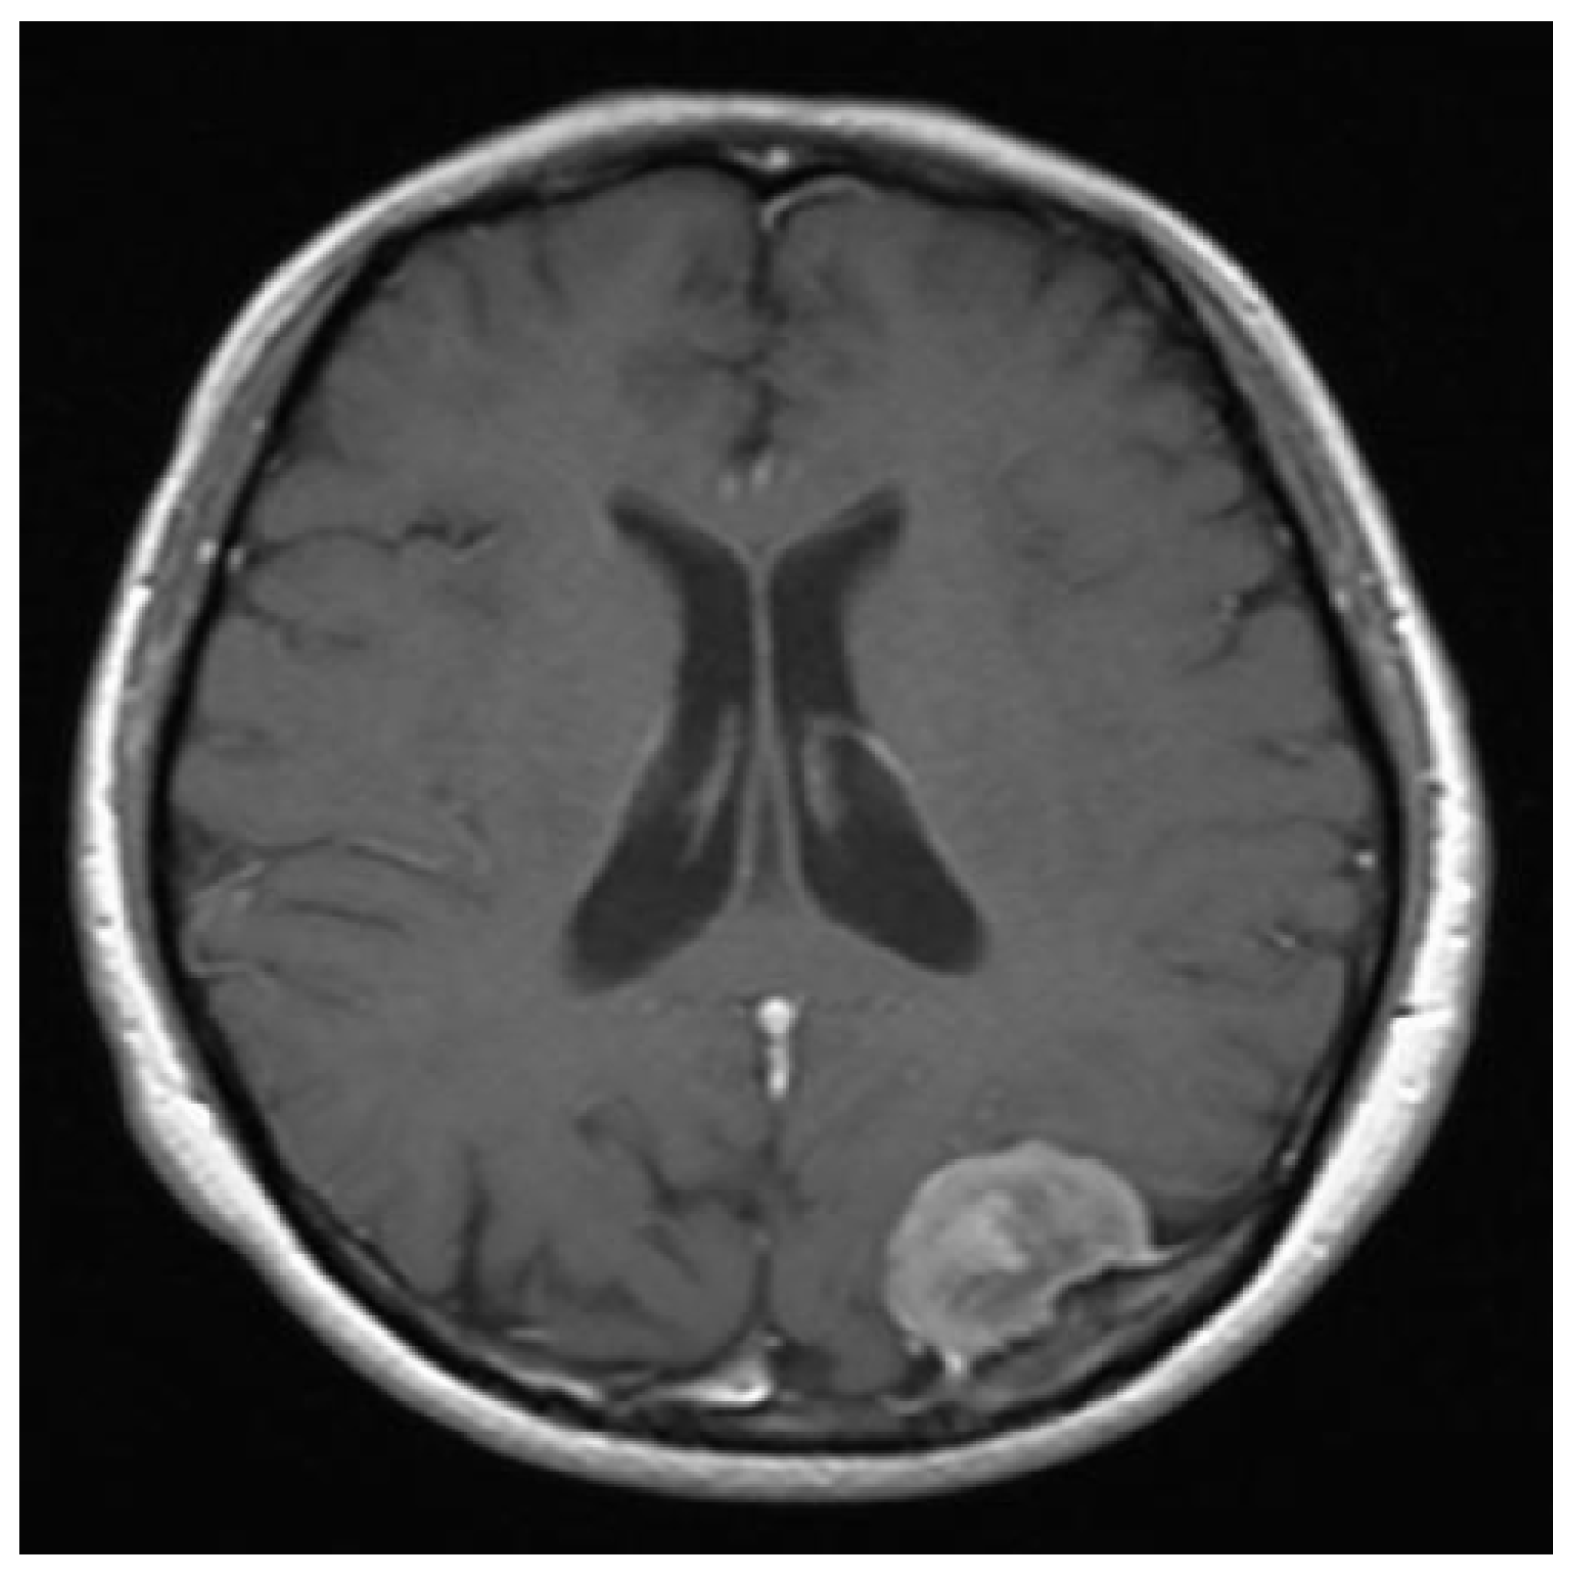

Moreover, and by accepting the fact that there is no still a satisfactory performance measure index for a image segmentation process [13]. So far, we utilize the subjective evaluation criterion [13]. However, it is important to note that even when this criterion is widely used, an untrained subjective evaluation may result in a mistake conclusion [13]. Then, by suing the subjective evaluation measure to our processed noisy images, our technique, and according to our numerical experiments, presents an acceptable performance. On the other hand, the Jaccard similarity coefficient has also been extensively used for the performance evaluation of image segmentation methods. Recall that the Dice similarity coefficient is related to the Jaccard one. Essentially, the Jaccard coefficient, also known as the Tanimoto coefficient, measures the overlapping of two given sets, or two images in logical format, where a value of zero indicates no overlapping, and a value of one indicates a perfect agreement. Hence, if two segmentation processes are going to be compared, the one with the bigger Jaccard coefficient (or closer to one) value will have the better performance. Therefore, we proceed as follows in order to validate our performance segmentation algorithm by employing this Jaccard similarity coefficient in comparison to the reference method. Given the original image shown in Figure 12, we add the speckle noise to it. See Figure 13. Then, by utilizing this noisy image, the processed segmentation results are depicted in Figure 14. Then we transform the clean image into a binary image (logical format) by invoking the command im2bw of Matlad with a thresholding level of . We called it Image A. After transforming the colored images shown in Figure 14 into gray-scale images, we also transform them to their binary formats by employing the same previous command at the same thresholding level too. We call them Image B and Image C, respectively. That is, Image B is the resultant binary image of our processed image, and the other one coming from the corresponding reference method. Now, we are interested in comparing the similarity between Image A and Image B with respect to the similarity between the Image A and the Image C by invoking the Jaccard method. By doing it, we obtain and , respectively. Hence, our approach has a better performance.

Figure 12.

The original clean image.

Figure 13.

The speckle noisy image with .

Figure 14.

The corresponding image segmentations. Left: Processed image by using our design. Right: Processed image by invoking the reference method.